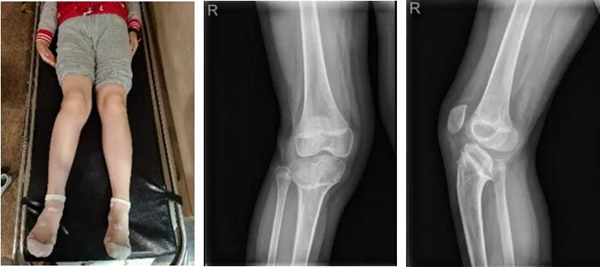

“醫(yī)生伯伯,我老是被同學(xué)說(shuō)腿怪怪的?!痹趶V州第一人民醫(yī)院9歲小李妹妹對(duì)醫(yī)生這樣說(shuō)道。據(jù)患者家屬描述,20169月小李妹妹因夾傷所致右下肢膝關(guān)節(jié)骨折,彼時(shí)當(dāng)?shù)蒯t(yī)院對(duì)其進(jìn)行了固定手術(shù)。但術(shù)后卻逐步出現(xiàn)右下肢畸形,且越來(lái)越嚴(yán)重以致步態(tài)異常。

△小李妹妹的腿部狀況;X線片

在丁煥文教授的安排下小李妹妹進(jìn)行X線片、CT、MR等傳統(tǒng)影像檢查,患兒X線片和CT掃描二維斷面圖像均發(fā)現(xiàn)患者右膝有嚴(yán)重后傾畸形改變。于是,拿到CT數(shù)據(jù)的樹(shù)蟻智能數(shù)字精準(zhǔn)外科云服務(wù)系統(tǒng)團(tuán)隊(duì)使用建模軟件對(duì)患者的全下肢進(jìn)行了精準(zhǔn)分離式三維重建,對(duì)小李妹妹重建后的患處進(jìn)行了解剖方位對(duì)齊和多方位的精準(zhǔn)三維測(cè)量,發(fā)現(xiàn)小李妹妹因?yàn)楣趋客鈧投嗄曛w畸形原因,右下肢短縮明顯,達(dá)41mm。

△臨床診斷:右膝部畸形

1.    矢狀面畸形:脛骨平臺(tái)后傾26.4736°

2.    額狀面畸形:內(nèi)翻6°

3.    右下肢短縮畸形(41mm